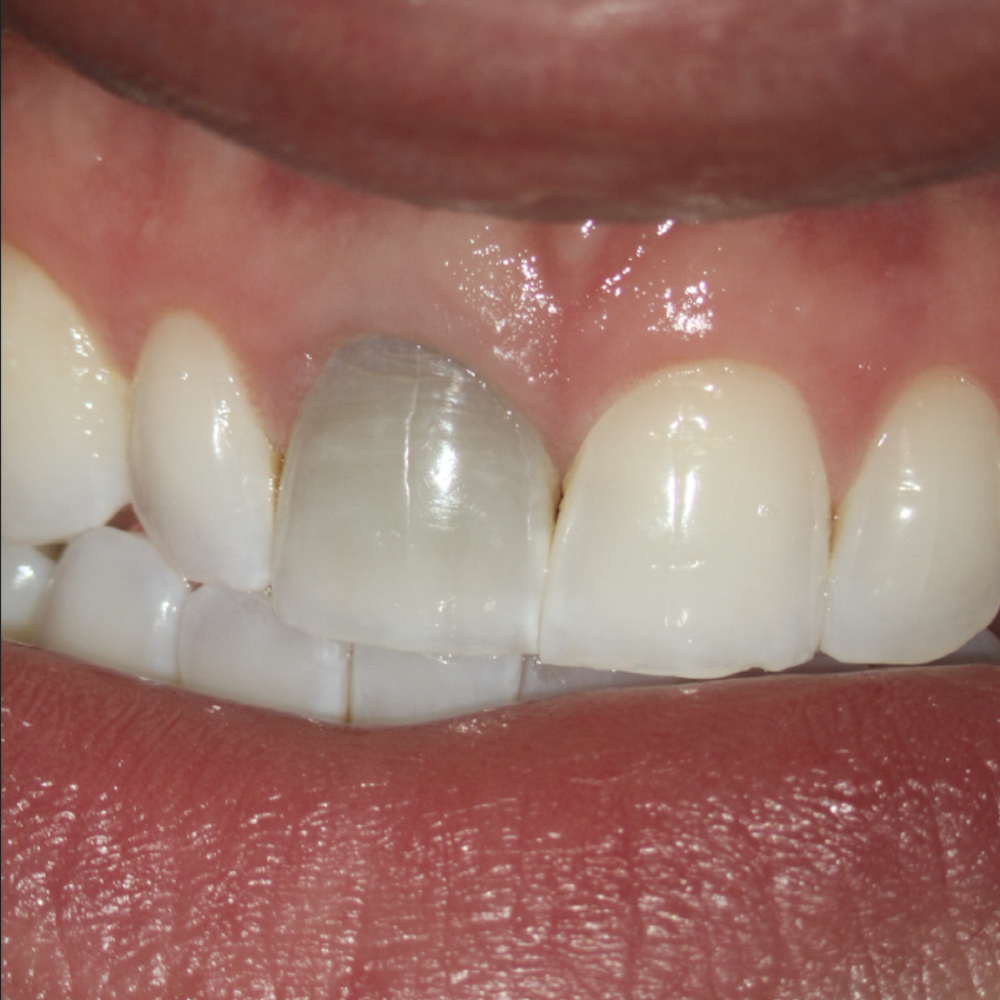

Resorption

Resorption is a condition where the tooth’s structure starts to break down, either from the inside out or from the outside in. It can be caused by trauma, inflammation, or other factors. Endodontic treatment for resorption involves removing the damaged tissue and reinforcing the tooth with materials that help prevent further damage. The aim is to save the tooth and maintain its functionality as much as possible.